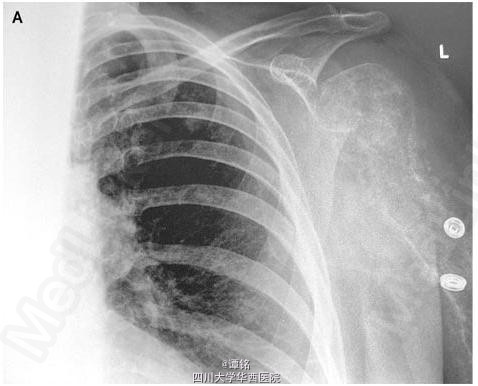

影像学发现胸部、头部转移癌。血清钙和碱性磷酸酶正常。左臂功能逐渐下降,平片发现肱骨近端骨质破坏,伴多处病理性骨折,推测是由于骨转移癌造成。